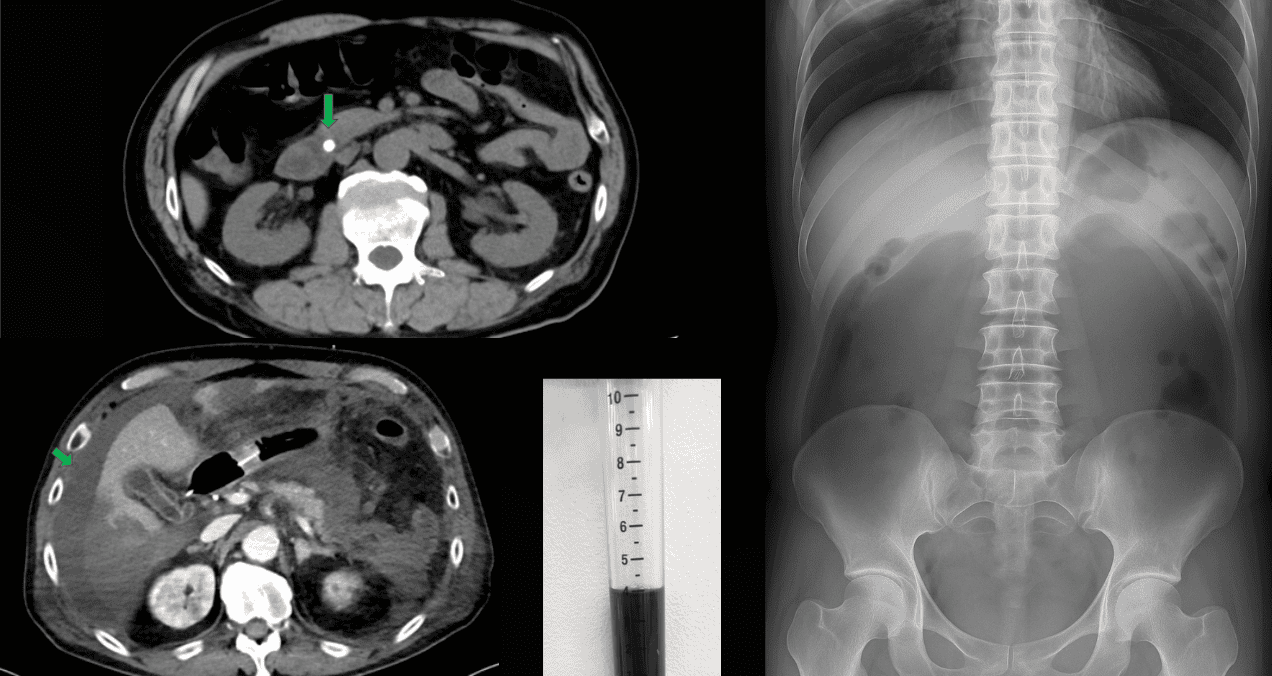

Tras una evaluación inicial en un centro menor, la tomografía computarizada (TC) abdominal reveló la presencia de un cálculo en el conducto colédoco (conducto que transporta la bilis desde el hígado y la vesícula biliar hasta el intestino delgado), acompañado de elevación marcada de proteína C reactiva (PCR) y amilasa pancreática.

Estos hallazgos condujeron al diagnóstico de colangitis aguda y pancreatitis aguda grave de origen biliar, por lo que se realizó una colangiopancreatografía retrógrada endoscópica (CPRE) con extracción del cálculo.

FIGURA 1: TC abdominal realizado en el hospital de referencia que demuestra un cálculo en el conducto biliar común (flecha verde) sin evidencia de ascitis. Foto: Caso Clínico - Kobori et al.

Ante el deterioro persistente, se inició hemodiafiltración continua por acidosis metabólica y fallo renal. Una nueva TC abdominal mostró ascitis leve (acumulación anormal de líquido en el abdomen) sin pseudoquistes pancreáticos.

FIGURA 2: TAC abdominal al ingreso del hospital que muestra ascitis de nueva aparición (flecha verde) sin evidencia de pseudoquiste pancreático. Foto: Caso Clínico - Kobori et al.